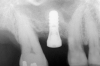

First, a periapical radiograph is taken to determine the amount of bone subantrally. It should be noted that a periapical film has an average error of 14%.23 Therefore, it is advantageous to take the radiograph in a manner that includes a marker (5-mm wide ball bearing) in order to be able to calculate the magnitude of radiographic error (Figure 1).

Figure 1  At tooth site No. 14, a periapical radiograph was taken with the long-cone paralleling technique. The radiographic ball marker measured 5.8 mm while its actual diameter is 5 mm. The enlargement is 0.8 mm, therefore the magnification error is 0.8/5 = 16%. By correcting for this error, a closer approximation of the amount of bone from the osseous crest to the sinus floor can be made.

Figure 1